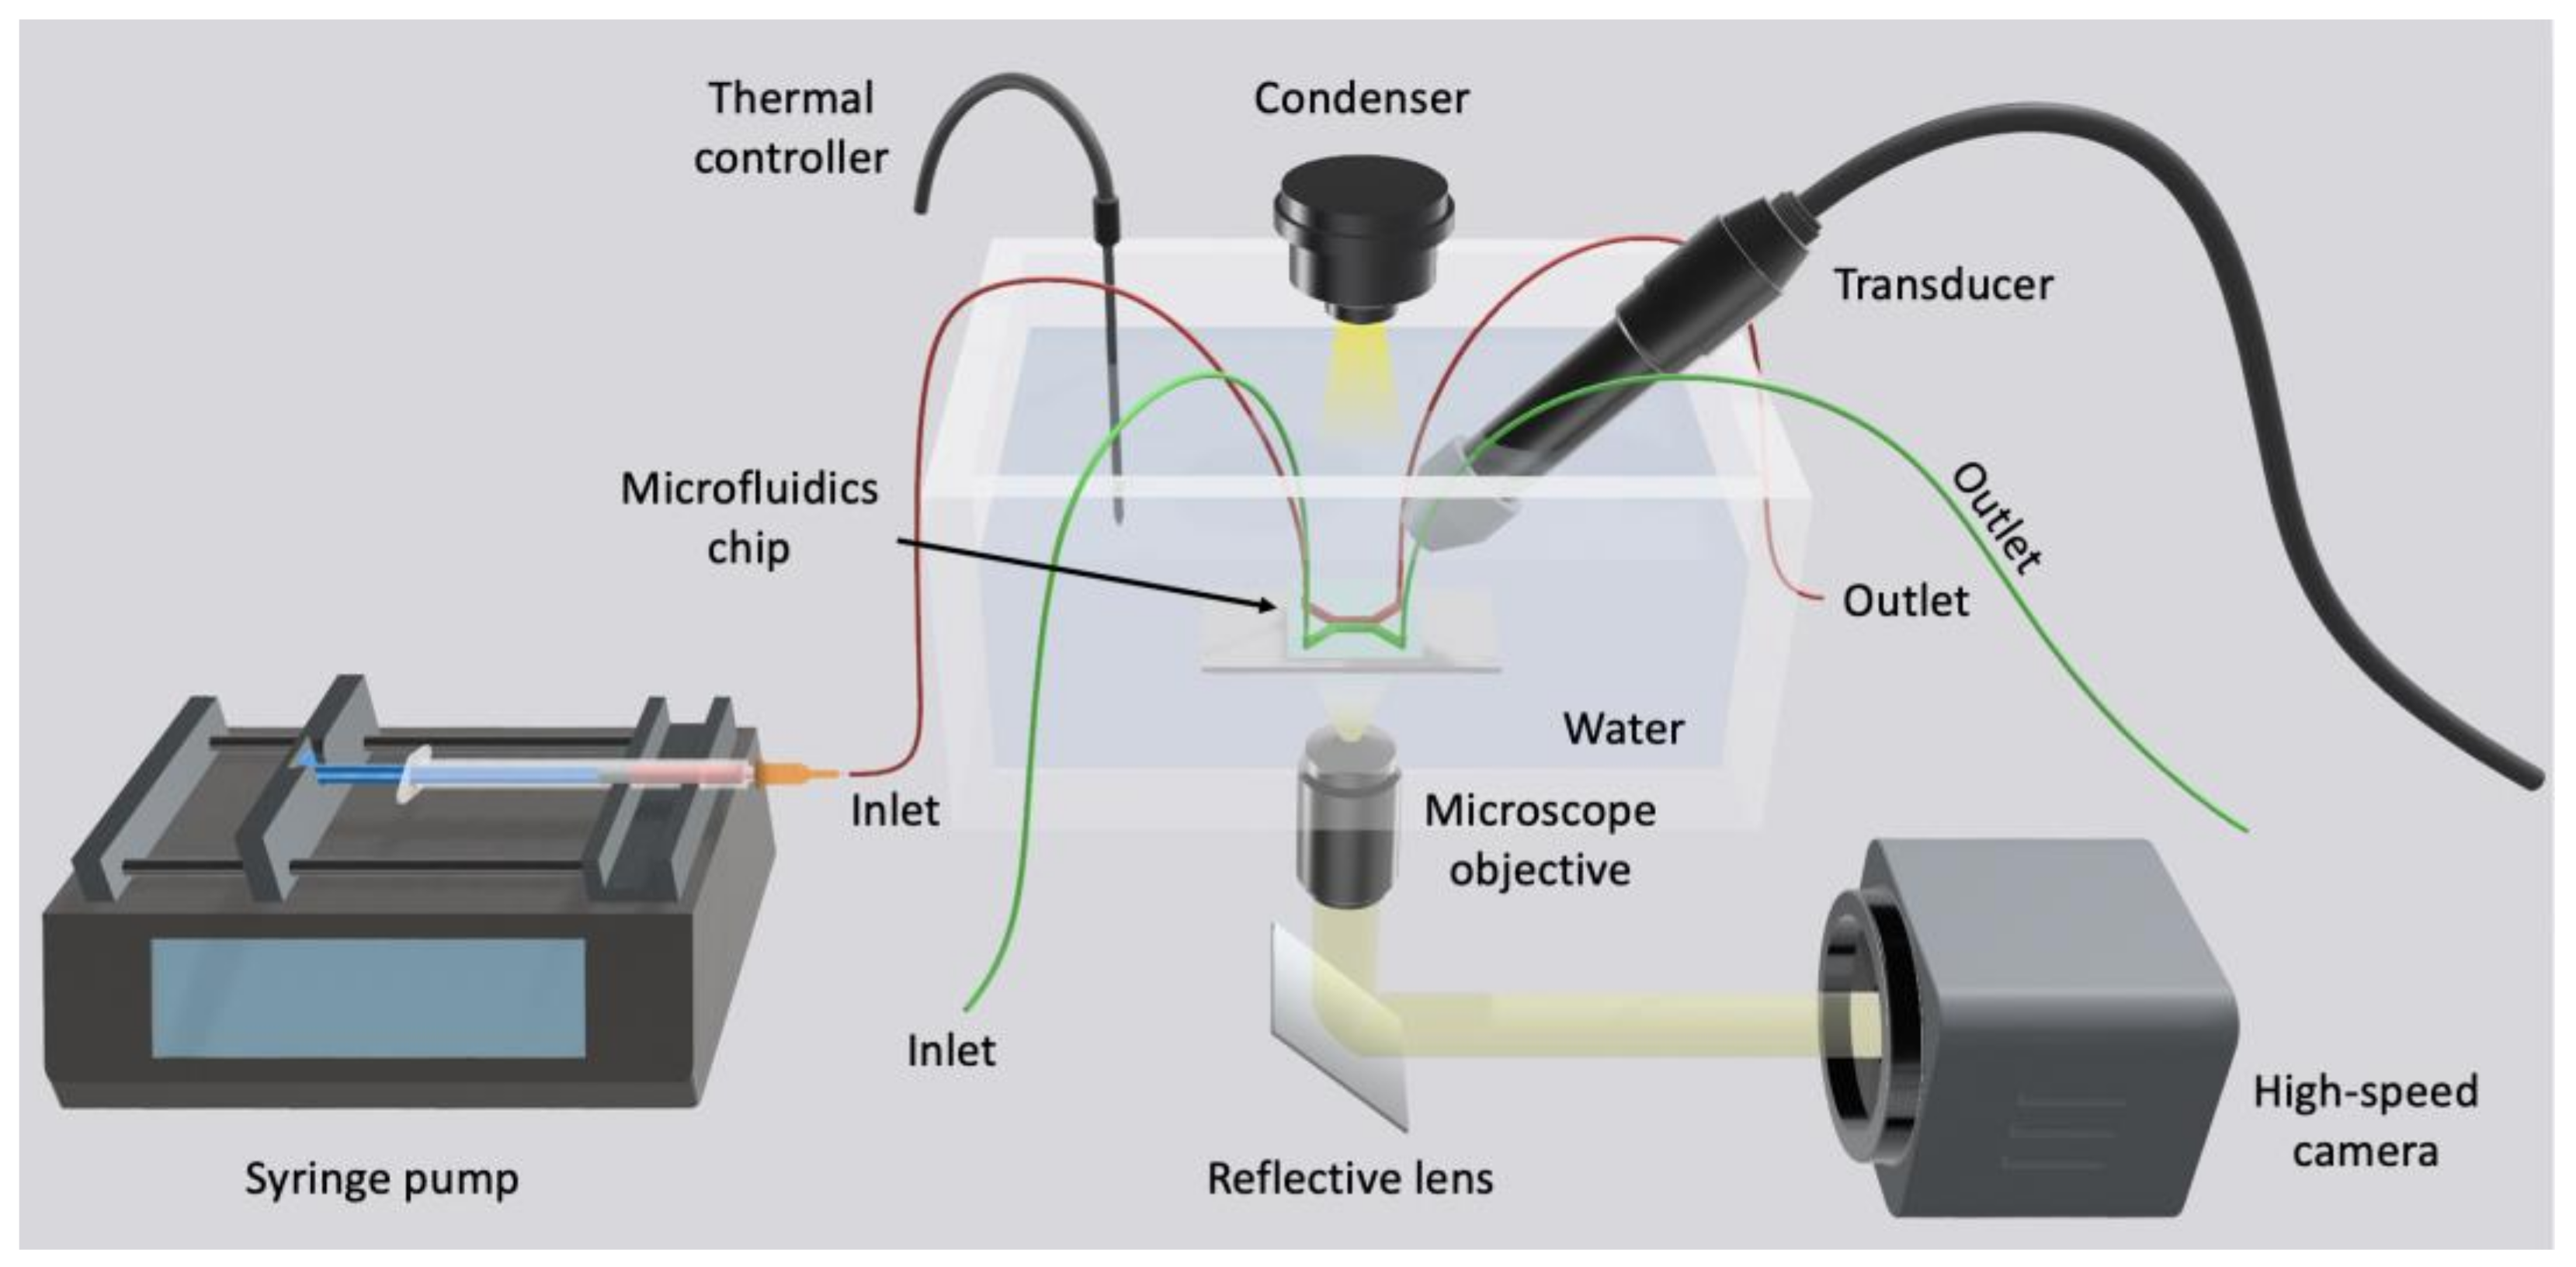

4.2.3. In Vitro Dynamic System